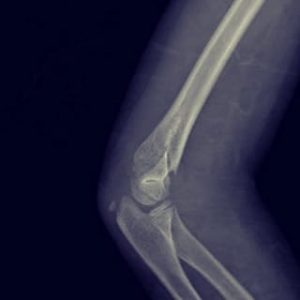

- Fracturas de codo

- Fractura supracondílea

Fractura supracondílea de humero